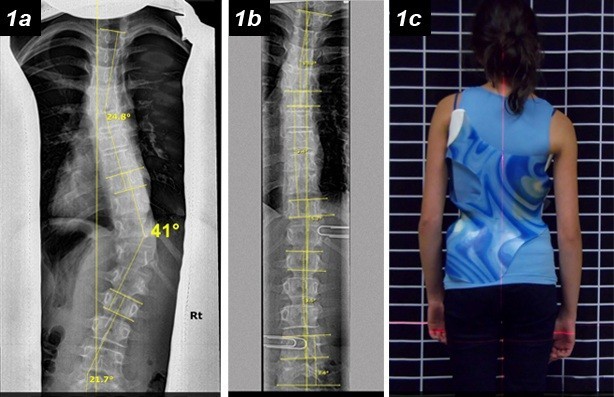

وجود اعوجاج متوسط في العمود الفقري

زاوية الانحناء تتراوح عادة بين 20 و45 درجة

زاوية اعوجاج كبيرة جدًا

وجود تشوهات واضحة في شكل الجذع

لذلك، لا يمكن الاعتماد فقط على درجة الاعوجاج، بل يجب تقييم شكل الانحناء ومكانه بدقة.